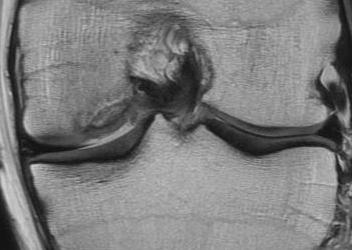

Technique Mosaicplasty Type 3 OCD

Harvest

- insert 4.5 mm chisel

- hammer to appropriate depth / 20 mm

- twist handle to remove

Debride base of OCD and reduce

Drill site of mosaicplasty with 4.5 mm drill